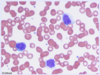

One symptom associated with bacterial endocarditis is septic arterial or pulmonary […].

One symptom associated with bacterial endocarditis is septic arterial or pulmonary emboli.

mnemonic: FROM JANE; may cause various nodes/lesions associated with bacterial endocarditis